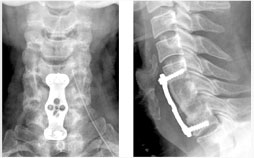

척추관 협착증의 방사선 소견

후외방 유합술(Posterlateral fusion) : 광범위한 후방 감압술 후 척추 외측에 있는 후관절과 횡돌기 간의 유합을 얻는 것.

- 충분한 감압을 얻을 수 있다.

- 신경 손상의 위험이 적다